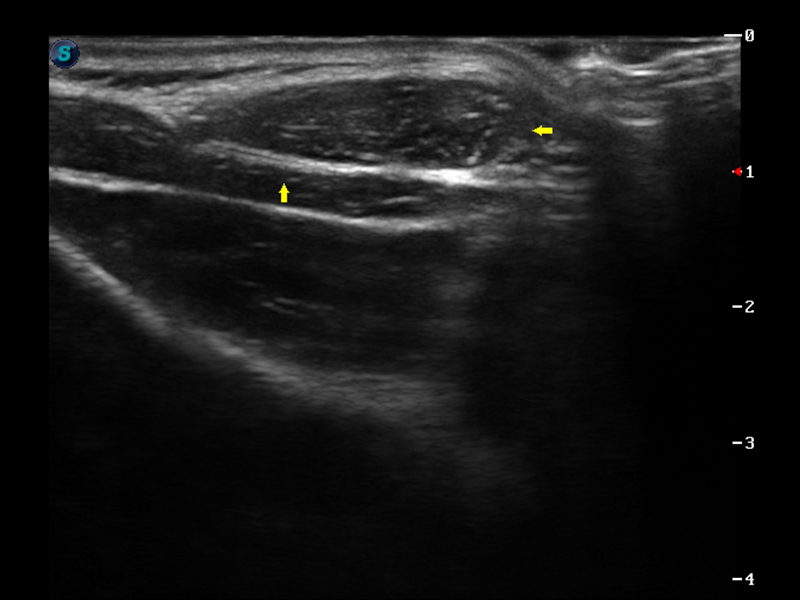

S9便携式彩色多普勒超声诊断仪是环球UG官网研发的高端便携彩超设备,外观设计新颖、产品性能卓越。S9在便携超声领域采用了突破传统的触摸屏交互设计,并以先进的软件硬件技术和设计理念,为您带来清晰的图像质量、稳定的工作性能和便捷的操作体验。

μ-Scan微米成像